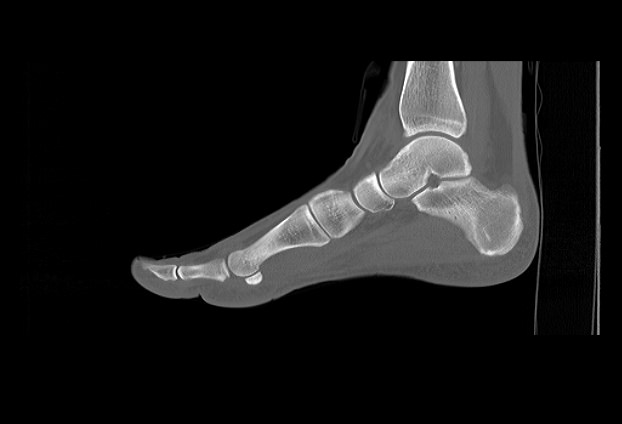

Стопа является самой удаленной частью нижней конечности и состоит из трех отделов: предплюсны, плюсны и собственно пальцев. Стопа представляет собой целый комплекс костей, соединенных между собой посредством тугих суставов.

Благодаря особенностям строения костей, а также наличию прочных связок, крепких мышц и сухожилий, стопа имеет сводчатую форму. Различают продольные своды и поперечный свод, которые обеспечивают эластичность стопы и ее амортизирующие свойства при ходьбе.

Наиболее точным и информативным методом обследования костных структур стопы является мультиспиральная компьютерная томография. КТ относится к лучевым методам исследования, то есть для визуализации внутренних органов применяется сканирование при помощи рентгеновского излучения, а затем полученные данные проходят цифровую обработку. В результате получается объемная реконструкция исследуемой области, которую можно увеличить, повернуть в разные стороны, оценить расположение анатомических структур и измененных участков в пространстве.

С помощью мультиспиральной КТ проводится точная диагностика травм стопы, позволяющая оценить расположение костных отломков. Метод КТ применяется для визуализации костей стопы при планировании хирургического вмешательства, затем в послеоперационном периоде для оценки правильности репозиции костных отломков и для контроля процессов регенерации кости.

Метод КТ наибольшую информацию дает о состоянии костных структур, так как кости в большей степени поглощают рентгеновские лучи и поэтому хорошо видны на снимках. Для повышения диагностических возможностей метода, в частности, для улучшения визуализации мягких тканей, мышц и связочного аппарата дополнительно используется контрастное усиление.